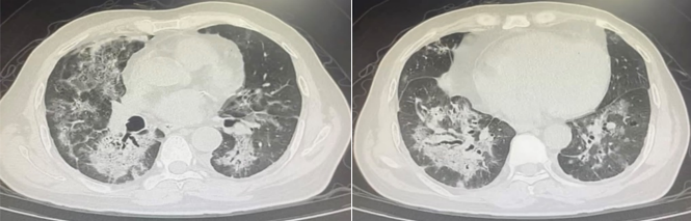

2023年1月12日,患者无明显诱因出现咳嗽,呈阵发性刺激性咳嗽,咳少量白痰。伴活动后气短,无发热、鼻塞、流涕、胸痛、咯血。自行口服止咳药物(具体不详)治疗,症状无明显缓解。2023年1月19日于当地医院住院治疗。查新冠核酸阳性。肺部CT示:沿支气管血管束分布的磨玻璃影,中心向四周扩散,考虑双肺感染;冠状动脉钙化;肝囊性灶;胆囊壁水肿(图1)。给予抗感染、输注丙球、新冠恢复期血浆等治疗。1月23日复查肺部CT示实变增多,右下肺有支气管充气征(图2)

图片

图1  患者肺部CT(2023-01-19)

图2  复查肺部CT(2023-01-23)